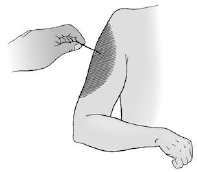

A figura representa, respectivamente, o dermátomo das raízes e nervo